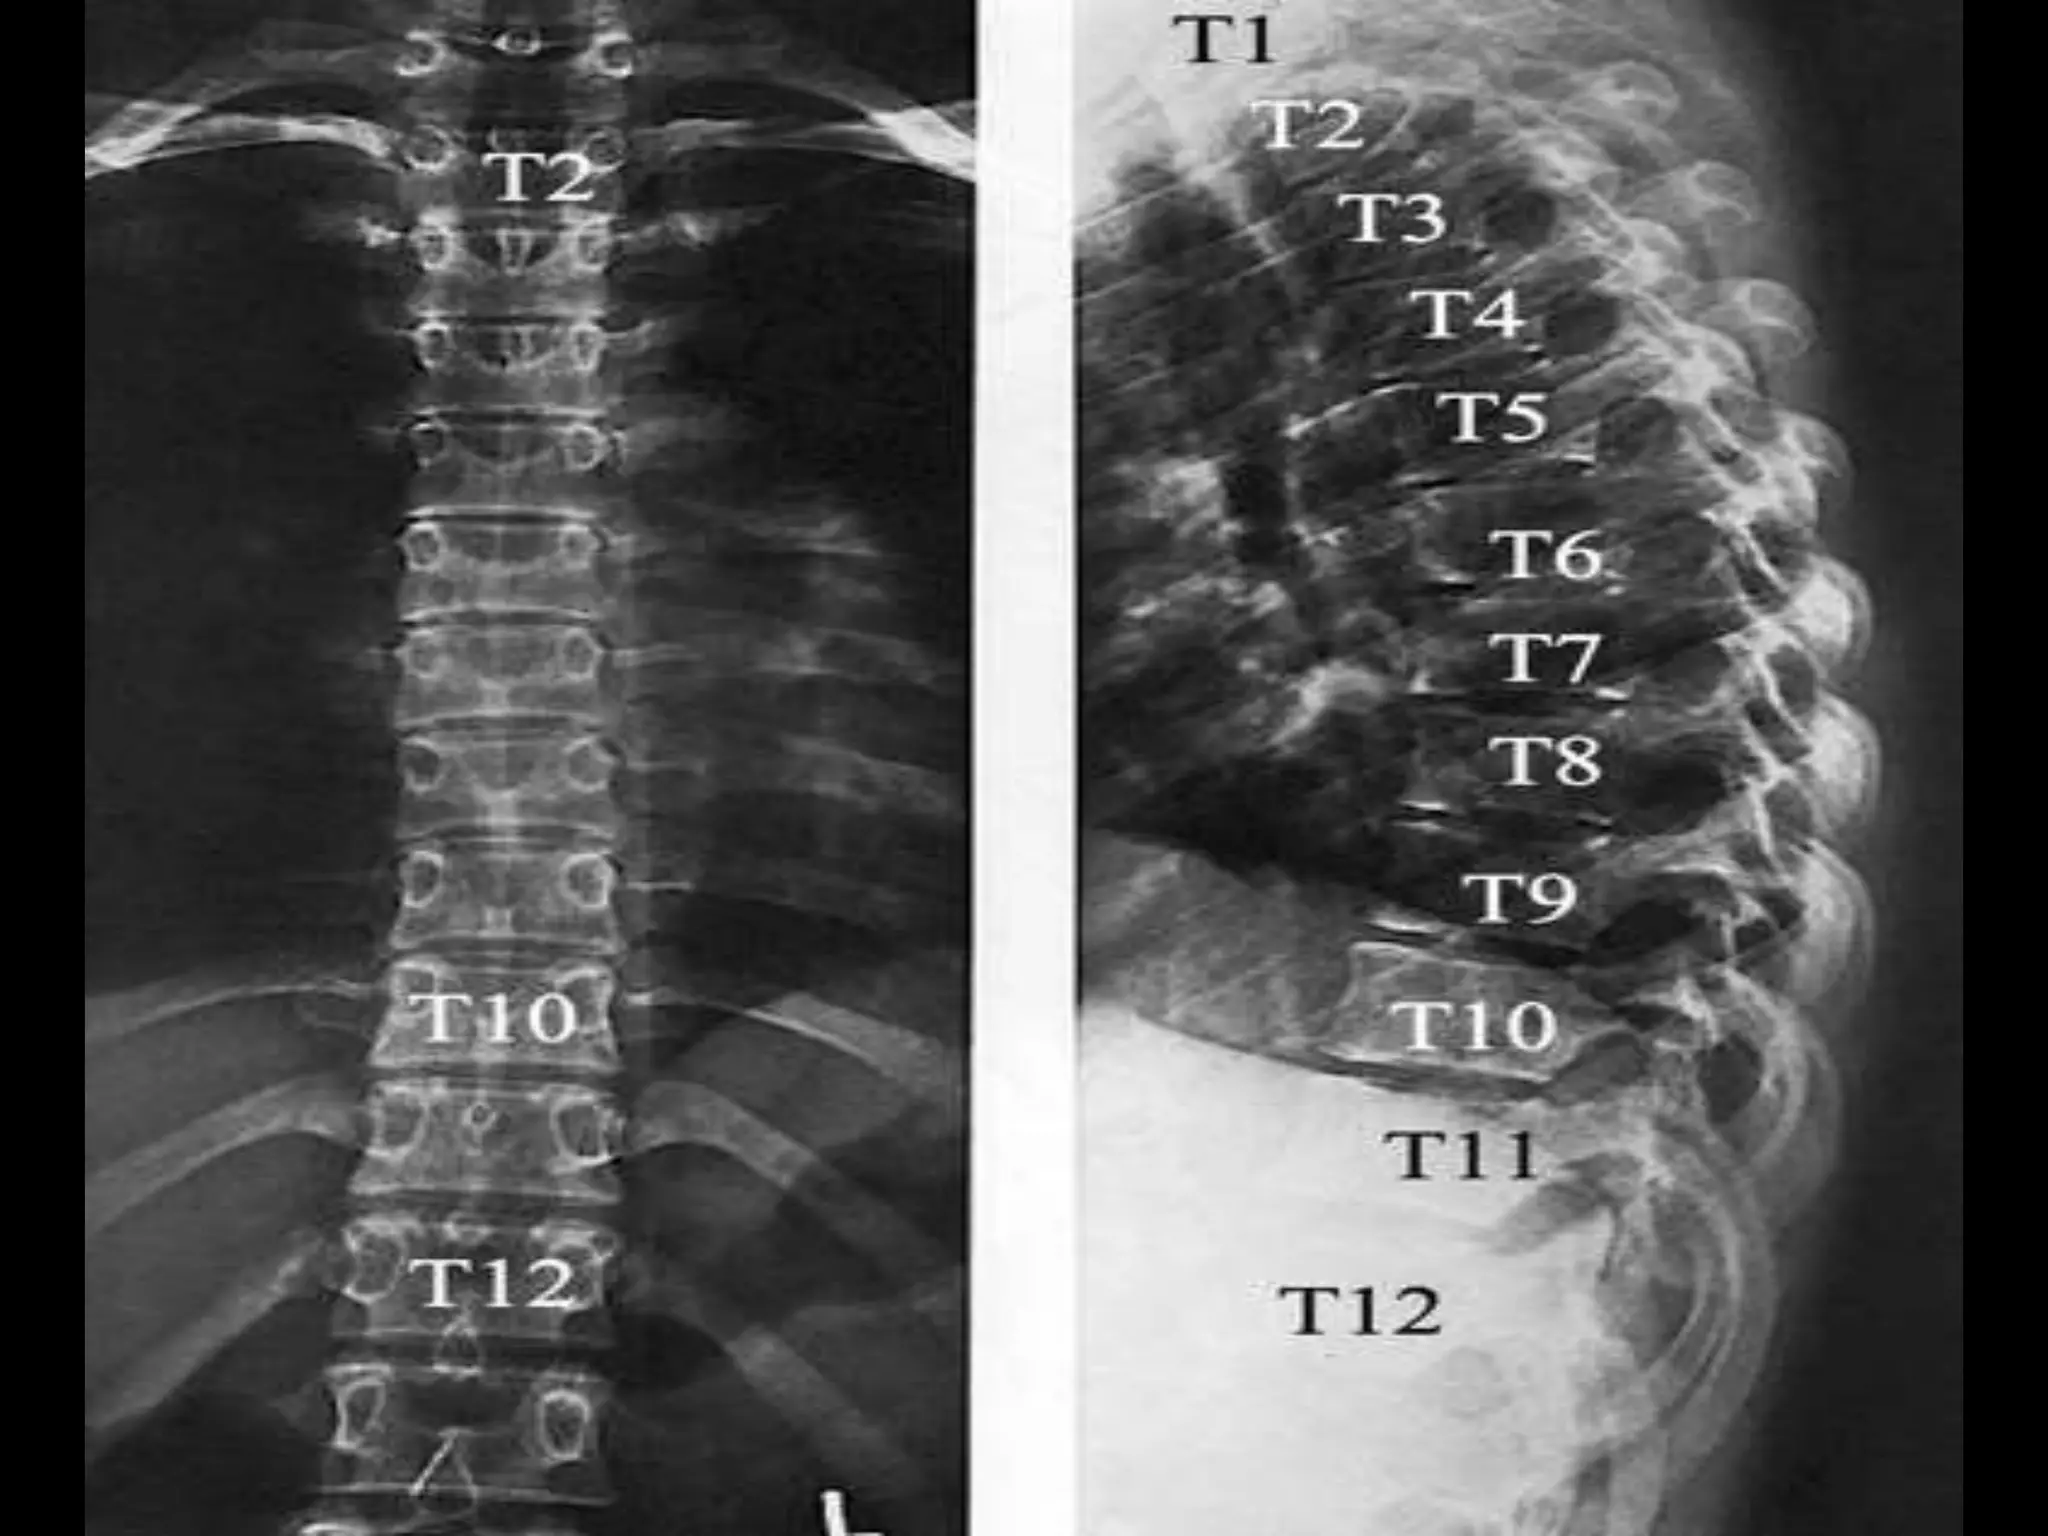

Thoracic Spine - AP & Lateral View.

Thoracic Spine -AP & Lateral View.